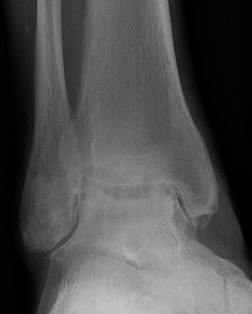

CT

Evaluate bone stock to determine if TAR is appropriate